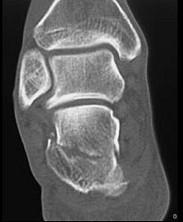

男,36岁,从高处摔下,脚部受伤,结合图像,最可能的诊断是 ( )A、舟状骨骨折B、楔骨骨折C、跟骨骨折D、骰骨骨折E、距骨骨折

问题 男,36岁,从高处摔下,脚部受伤,结合图像,最可能的诊断是 ( )

选项 A、舟状骨骨折 B、楔骨骨折 C、跟骨骨折 D、骰骨骨折 E、距骨骨折

答案 C